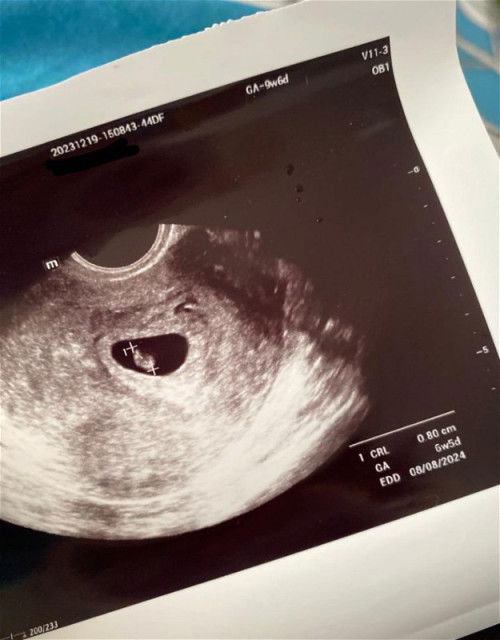

UPDATE: Thank you for your kind words. And calming me. Unfortunately Dr dah sahkan saya missed miscarriage and skrg darah fresh always keluar. Takda rezeki kalini tapi terkesan jugaklah sbb ttc lama kan. Doakan saya ya dipermudahkan urusan nak keluar janin βΊοΈ > > Hi mommies, nak tanya ada tak yang sama mcm saya bila repeat scan 2 minggu lagi kandungan lari jauh. Kira janin tu membesar kira2 4-5 hari dalam tempoh dua minggu tiap kali saya scan. 5x kali dah scan latest scan ni patutnya kandungan 9w6d (nak masuk 10w) tapi bila scan 6w5d, baby ada heartbeat semua okay je. Cuma lambat sangat janin nak membesar. Ikutkan edd saya 17/7/24 ni bila repeat scan je mesti lari jauh dan latest scan dah jadi 8/8/24 π’ Saya period irregular & ada pcos serta retroverted uterus. Cycle period 38-45 days tgk apps. Ada ke tips nak bagi besarkan janin? Ke memang normal usia kandungan baby lari dari first day last period walaupun baby okay? #pleasehelp #firstmom #bantusharing